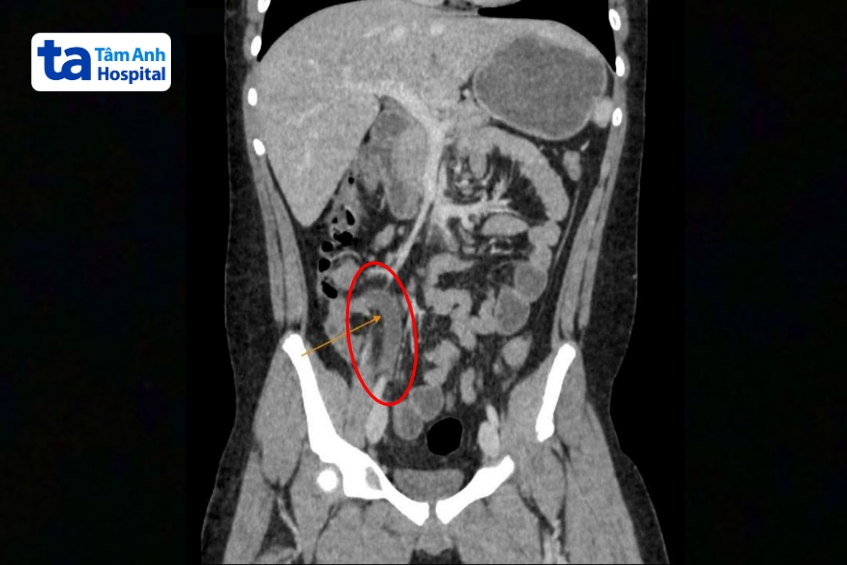

Chụp CT phát hiện ruột thừa đường kính 12mm (trên 6 mm là viêm), kèm sỏi phân 8 mm gây bít tắc lòng ruột thừa. Sỏi phân gây tăng áp lực trong ruột thừa, chèn ép mạch máu, dẫn đến hoại tử và vỡ ruột thừa trong thời gian ngắn, buộc phải phẫu thuật khẩn cấp.